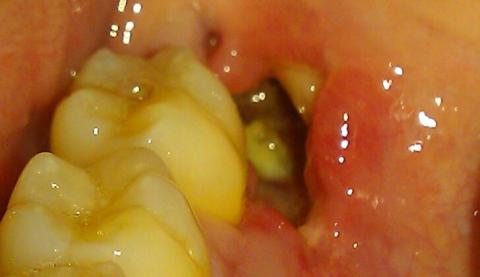

But in a devastating error, the dentist misread the chart and extracted the healthy molar next to the decayed one. The shock was immediate, but the real agony was just beginning.

Days later, Leo was in excruciating pain. A foul smell filled his mouth, and even cold air felt like a knife in the jaw. The empty socket was a dry, painful crater. The new dentist had not only pulled the wrong tooth but had also failed to protect the correct socket, leading to a severe case of Alveolar Osteitis—Dry Socket.

A dry socket occurs when the blood clot that forms after an extraction is dislodged or dissolves, exposing the underlying bone and nerves.